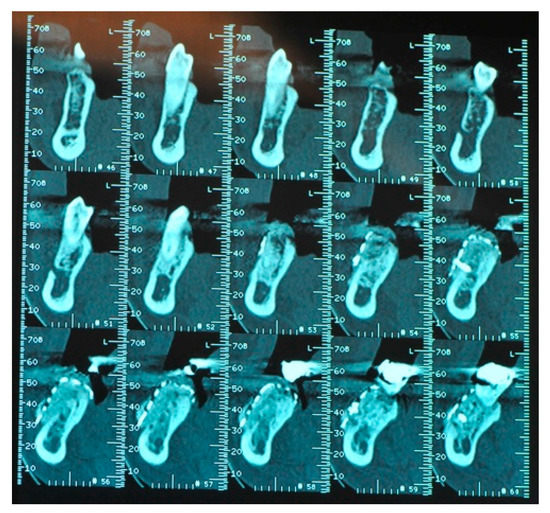

- The presence, clinically and radiographically (intraoral radiographs, panoramic, CT scans) assessed, of horizontal, vertical or mixed bone defects of the maxillary bones in particular the presence of residual bone <8 mm in height and <5 mm in width.